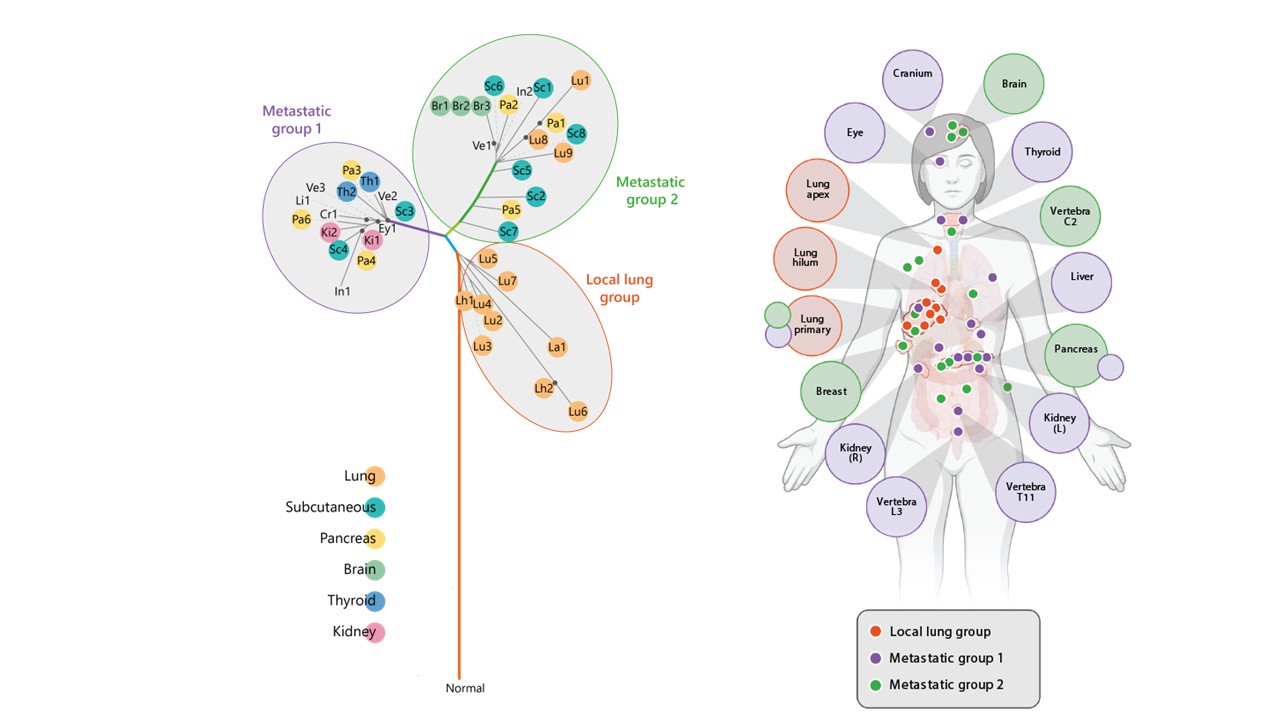

Following the evolving genetics of cancer

Through a broad transdisciplinary project and extensive DNA sequencing analysis, MWC scientists have identified how different metastases evolve through a variety of genetic changes

read the full story